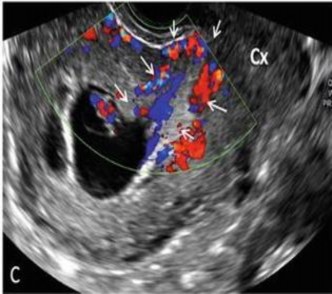

Hình 1.4. Hình ảnh tăng sinh mạch máu vùng sẹo mổ lấy thai [23]

Siêu âm Doppler giúp phát hiện tuần hoàn bàng hệ xung quanh túi ối, giúp xác định vị trí túi ối và diện rau bám ở SMLT và hình ảnh mạch máu đâm xuyên vào bàng quang. Tiêu chuẩn của kỹ thuật siêu âm này giúp phân biệt với túi ối bám tại ống CTC, eo tử cung hay là đang sẩy thai [24]. Trong trường hợp thai sẩy, túi ối đã bong ra khỏi vị trí rau bám nên không có hình ảnh mạch máu quanh túi thai, ngược lại sẽ là hình ảnh có nhiều mạch máu quanh chu vi túi ối tại vùng SMLT. Đã có những nghiên cứu ghi nhận khi tiến hành siêu âm Doppler, vận tốc dòng chảy qua các mạch máu xung quanh lớp tế bào nuôi trong chửa SMLT thấp hơn trong trường hợp thai trong tử cung, với vận tốc đỉnh lên 20 cm/s và mức trở kháng dưới 1.

(4) Tăng sinh mạch máu quanh khối thai qua siêu âm Doppler;